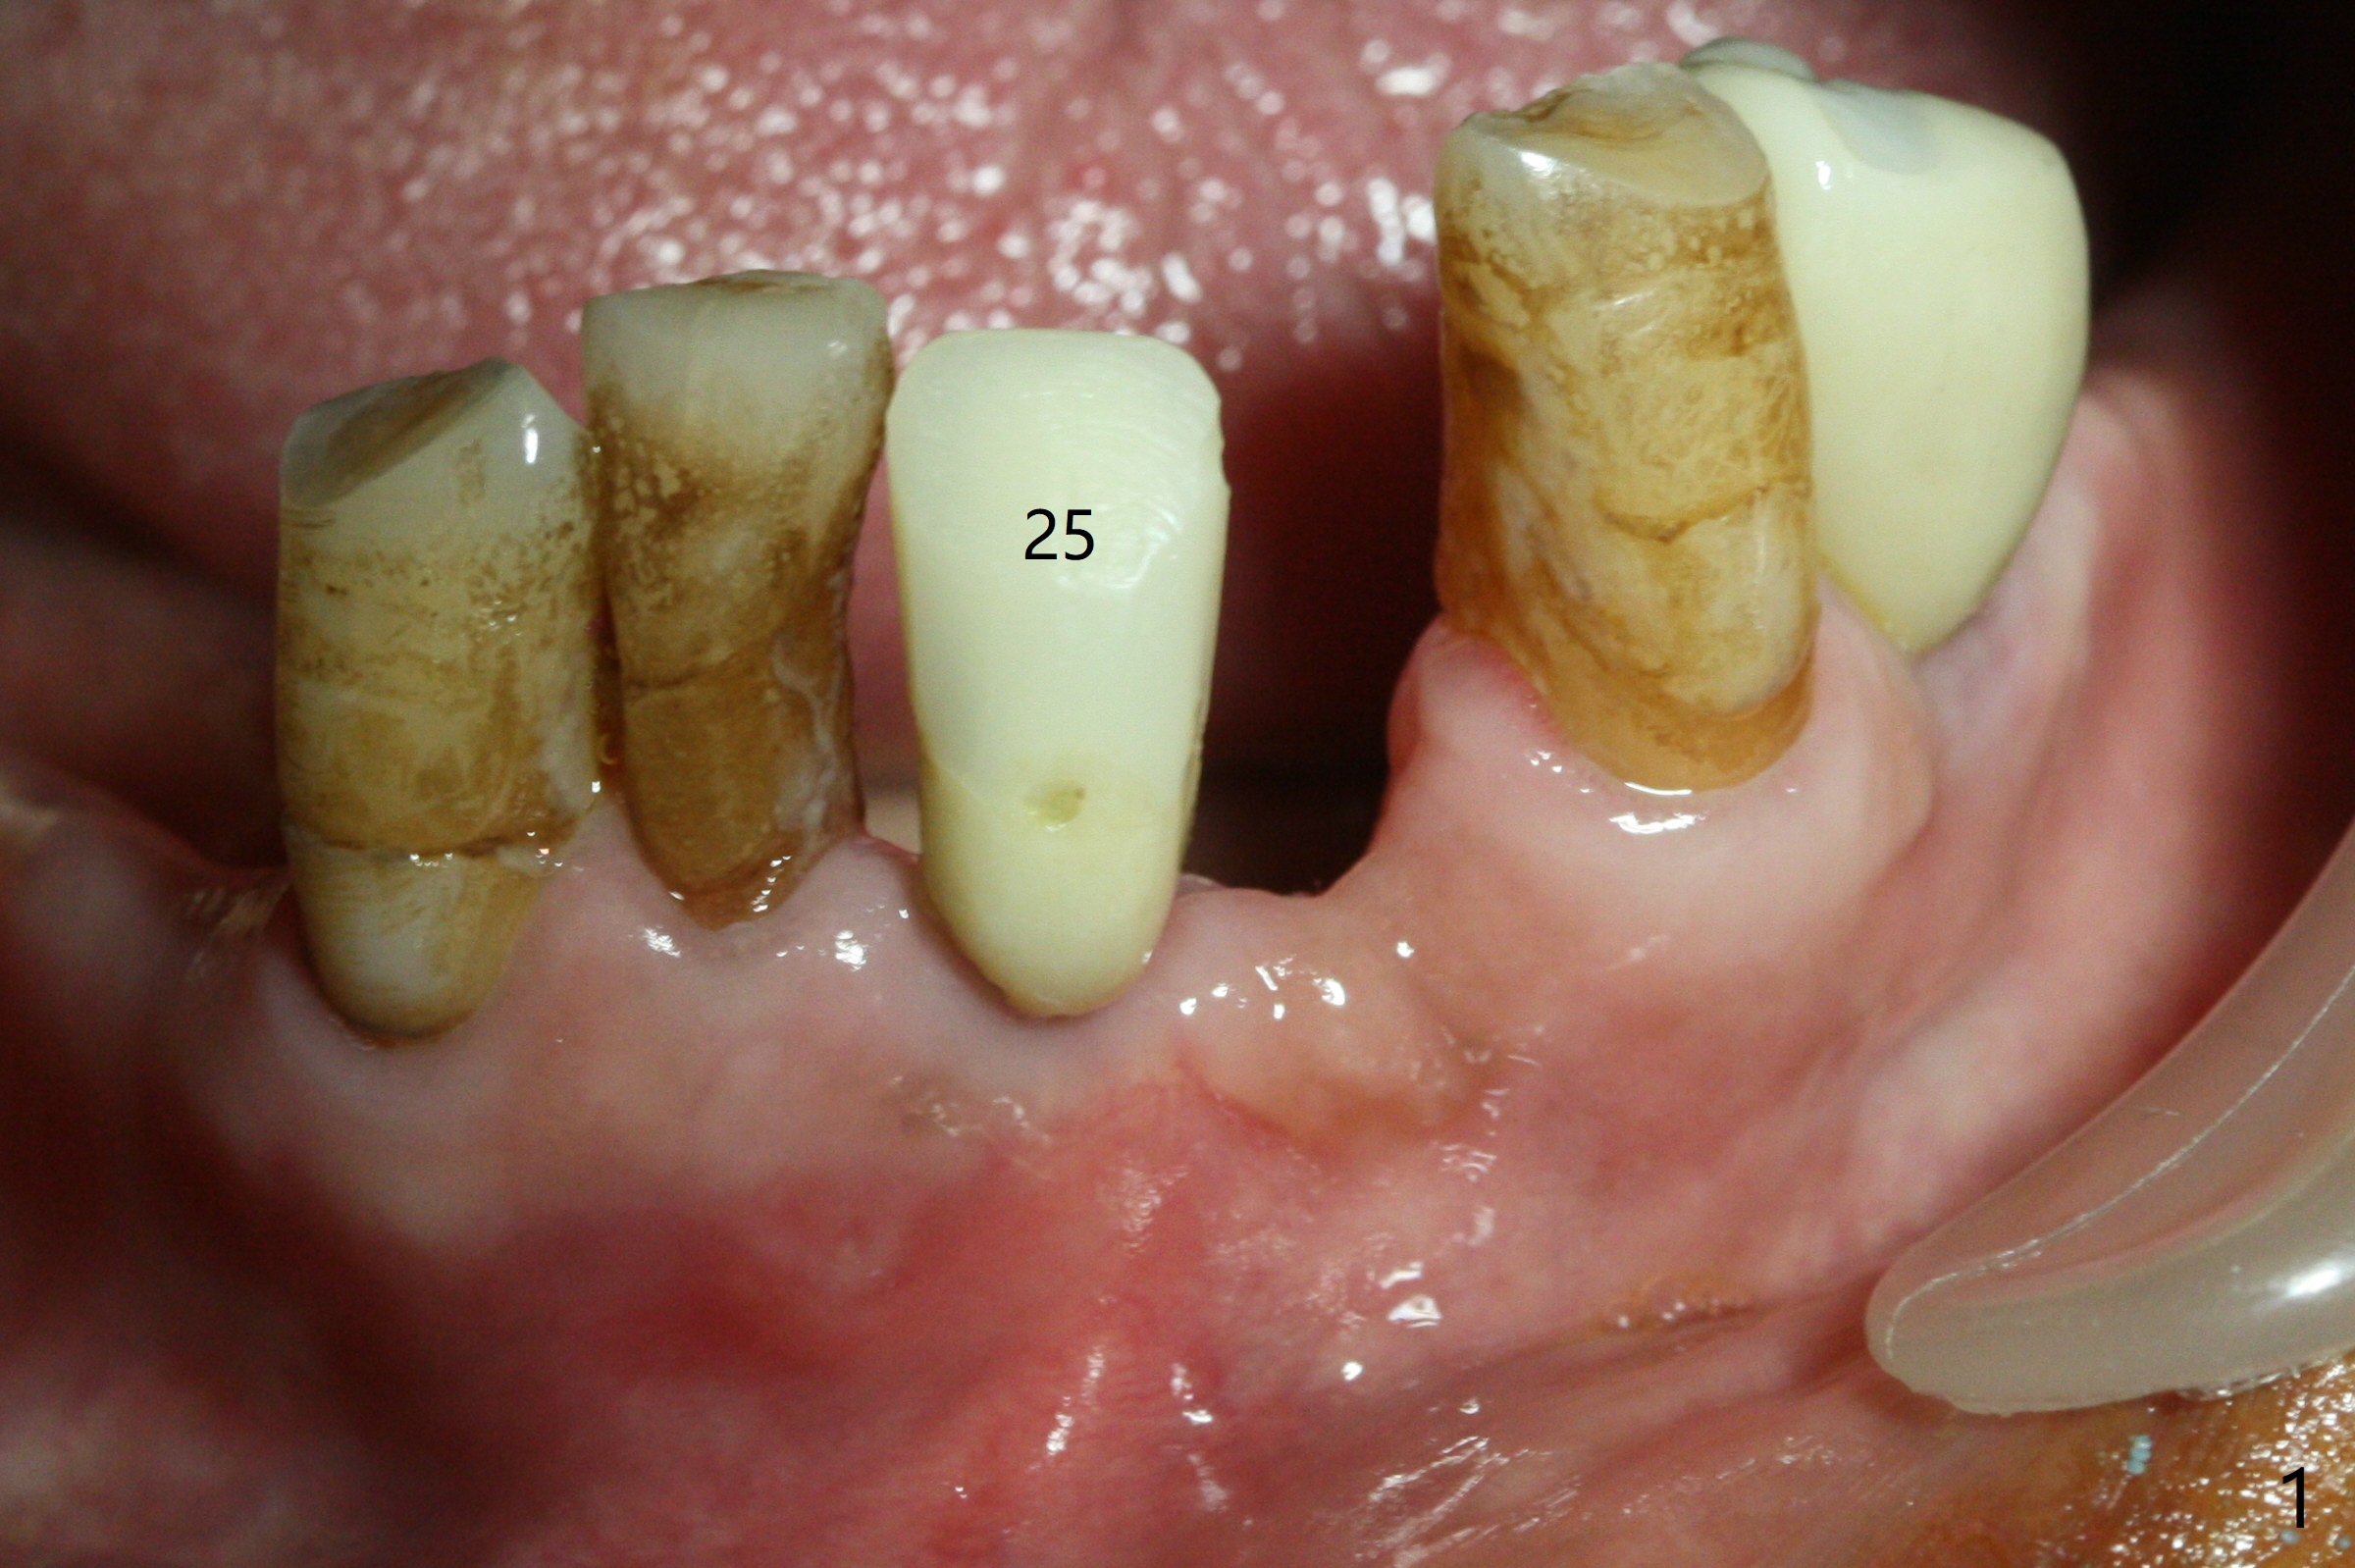

Two and a half months after loss of a 2 mm 1-piece approximately at #23 (Fig.1,2), it appears that the site of #24 (Fig.3 line) is more appropriate because the bone is higher. After removal of the pointed ridge top, osteotomy is initiated with 1.2 mm drill, followed by 1.5 mm one (Fig.4,5). When the 1.5 mm drill is removed, the new osteotomy (Fig.6 *) is mesial to the old one (^). Since the ridge is narrow (Fig.5,6), a 2x14(4) mm 1-piece implant is placed with GBR (Fig.7). Due to overprep, the torque is 20 Ncm. No immediate provisional is fabricated. Instead periodontal dressing is applied around these 2 implants. Two separate provisionals are fabricated when the wound heals. The one at #24 does not stay. The implant at #24 appears to osteointegrate 6.5 months postop (Fig.8). When the crowns are cemented, the margin is supragingival (Fig.9,10). Water Pik is recommended.